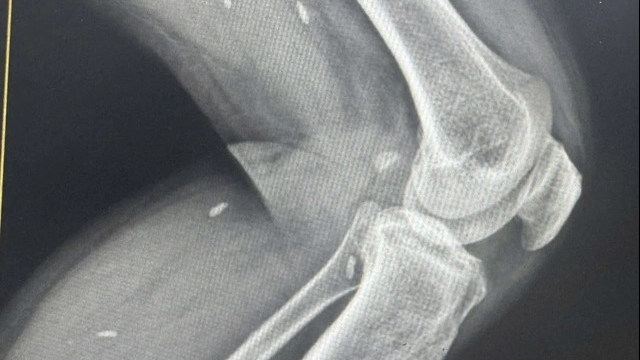

| Bệnh nhân suýt phải cắt bỏ chân vì tự xử lý mụn nhỏ tại nhà, khiến nhiễm trùng lan rộng, đe dọa hoại tử và tính mạng |